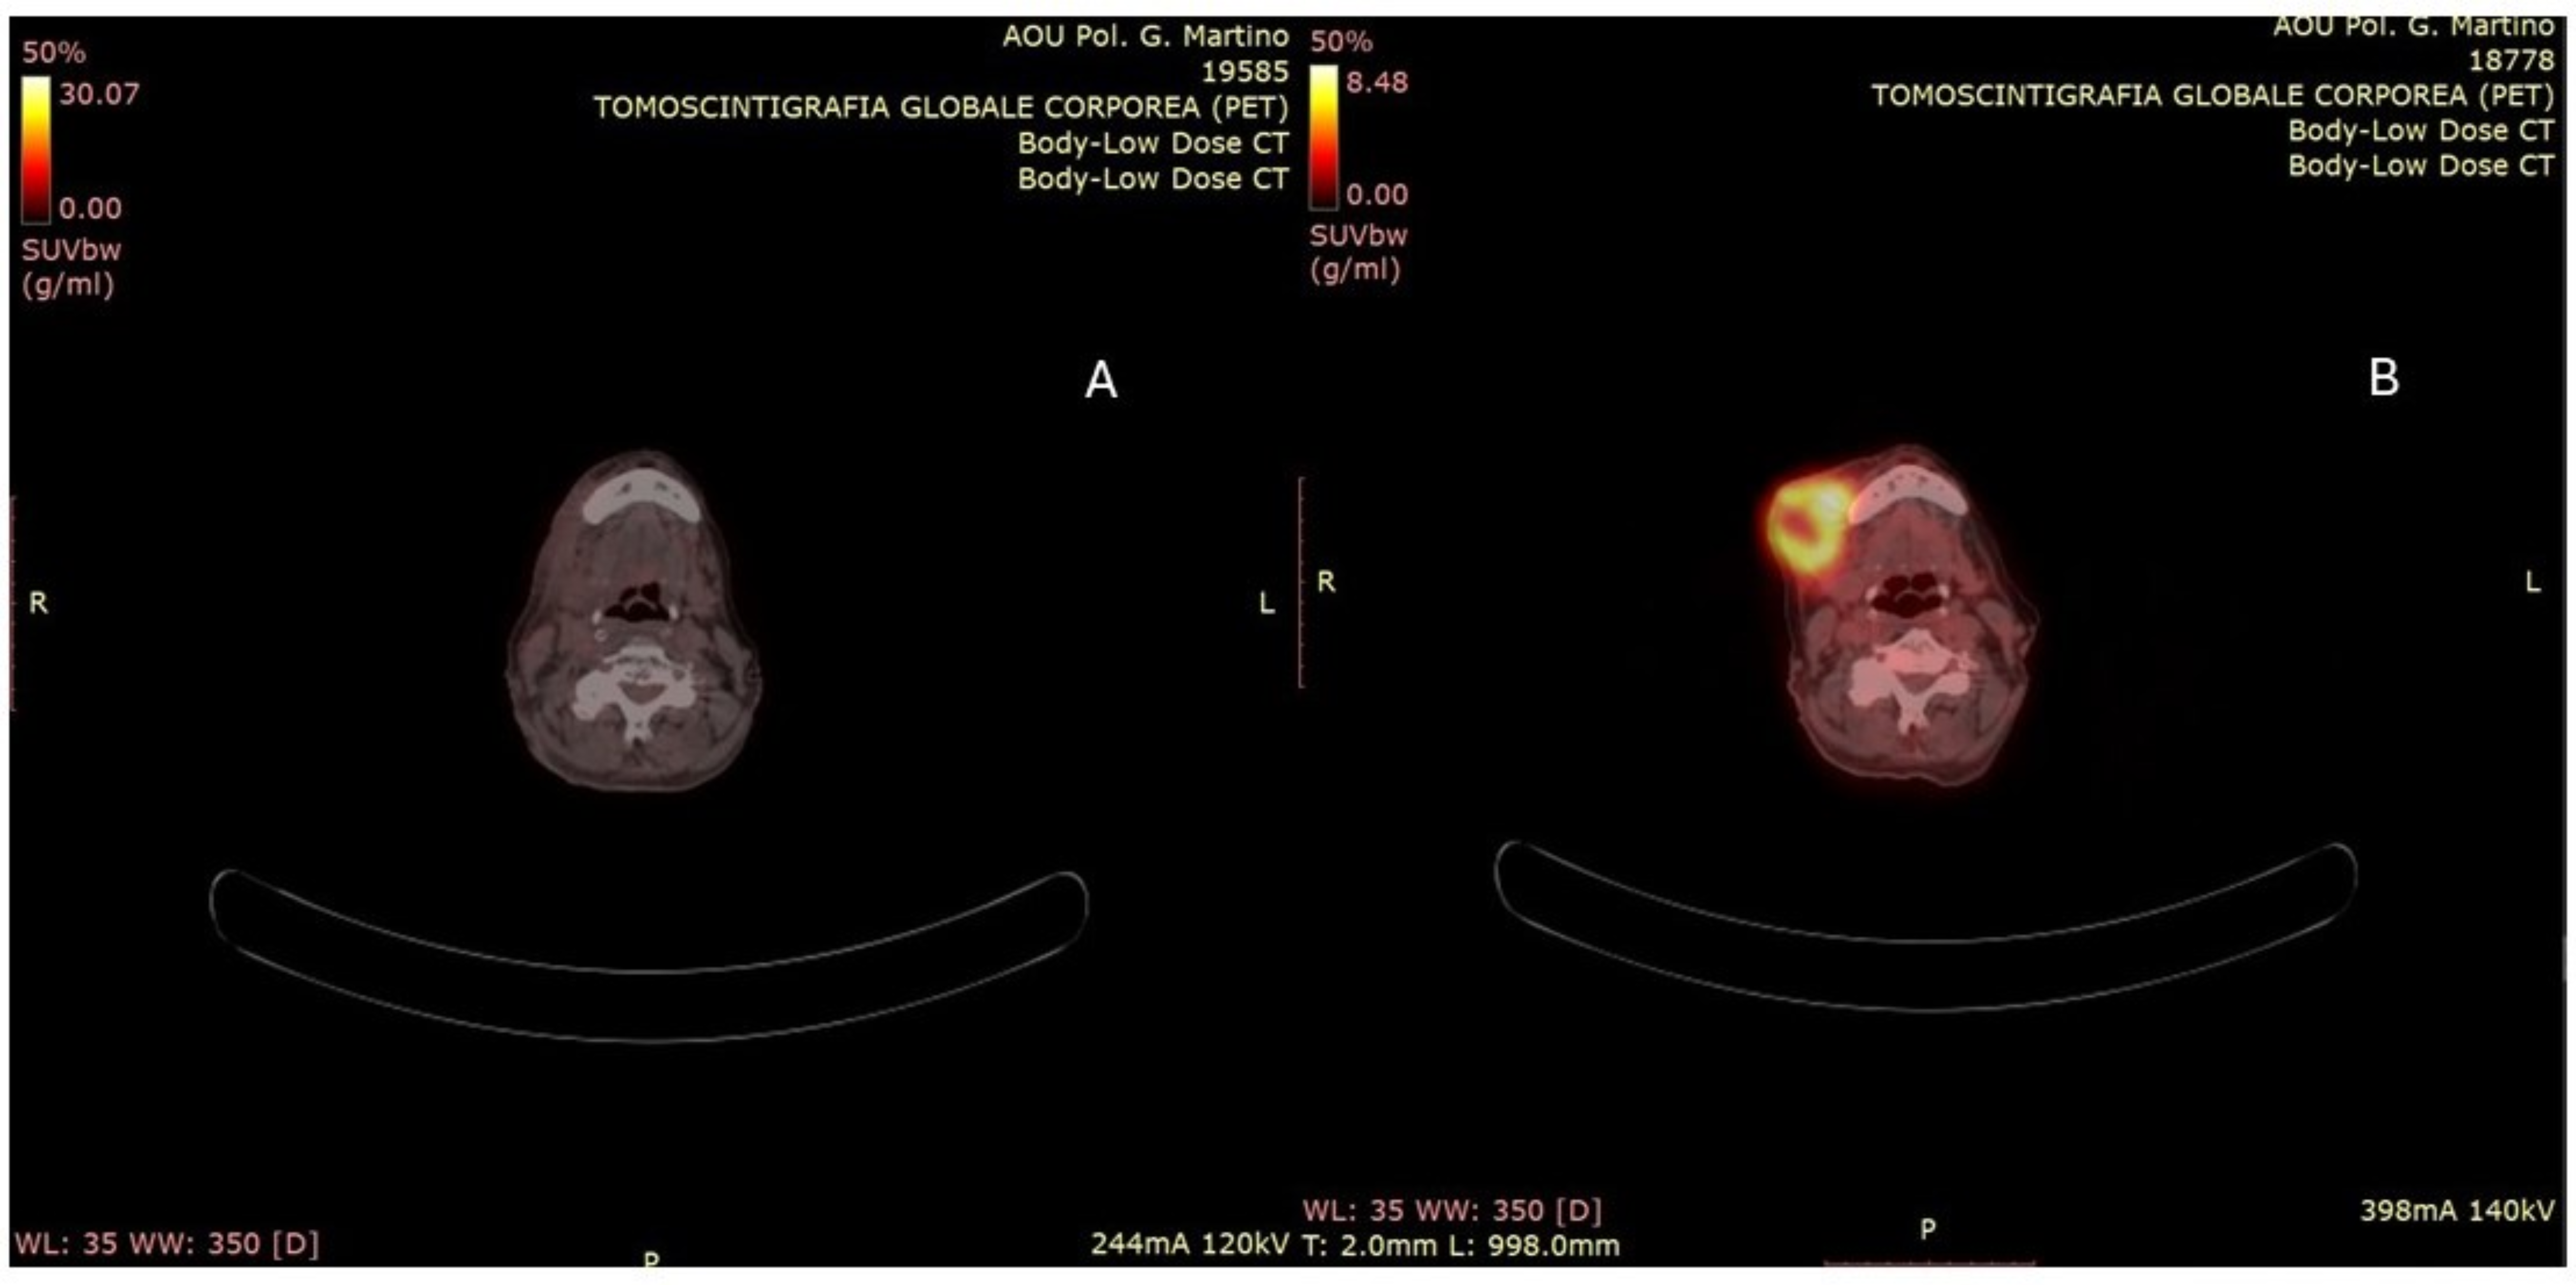

2. Case Presentation

3. Discussion